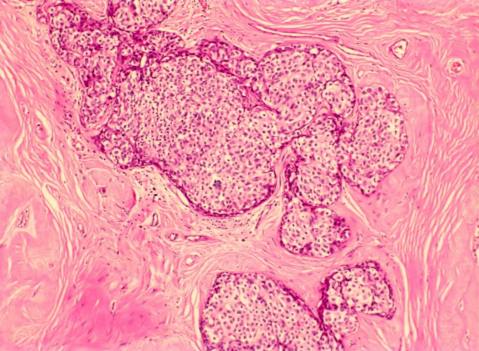

Meme konusunda deneyimli bir radyolog tarafından yapılan “tru cut” yöntemi ile yapılan “core needle” biyopsiler daha invazif olmakla birlikte histopatolojik tipleme yapılması ve reseptör çalışmasına olanak tanır. Ayrıca meme koruyucu cerrahi öncesinde cerrahın ameliyat stratjisine de katkıda bulunur. Bu tip biyopsiler steriotaktik olarak ya da USG eşliğinde yapılmaktadır. Kliniğimizde benign lezyon olarak kabul edilmiş fakat aile öyküsü ve tüp bebek tedavisi görmüş bir hastamızda radyolojik değerlendirmedeki şüphe doğrultusunda palpe edilemeyen bir adenofibroma lezyonu içinde daha sonra yapılan işaretli biyopside DKİS lezyonu saptanmıştır (Resim 1).

Resim 2. Adenofibroma içerisinde gelişen DKİS lezyonu (Işık mikroskobu x10 ve x40 büyütme)